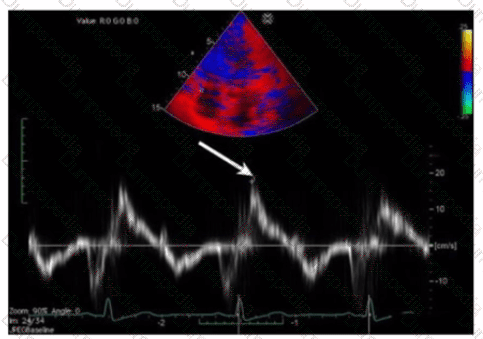

Which patient positioning is best for obtaining the waveform seen in this image obtained by a non-imaging transducer?